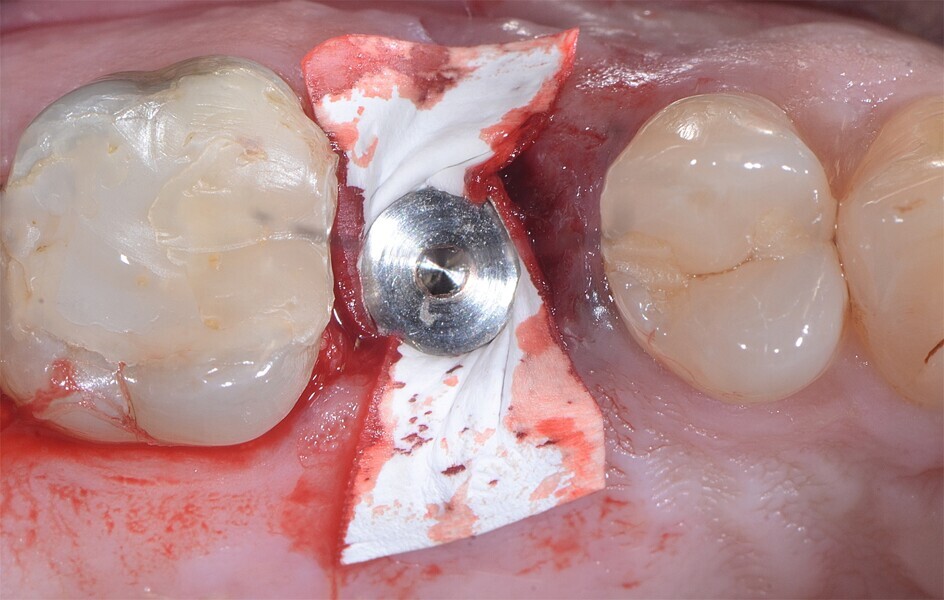

Fig. 31 : Mise en place d’une membrane de collagène à titre de barrière de protection et suture.

Fig. 32 : Mise en place d’une membrane de collagène à titre de barrière de protection et suture.

Fig. 33 : Mise en place d’une membrane de collagène à titre de barrière de protection et suture.

La crête alvéolaire au niveau du site de la molaire inférieure était trop étroite pour permettre la pose prédictible d’un implant sans une augmentation osseuse préalable. Des implants deux pièces en zircone ont été mis en place, simultanément à une augmentation osseuse latérale, au moyen d’une allogreffe et d’une membrane de collagène résorbable (Figs. 25–34).